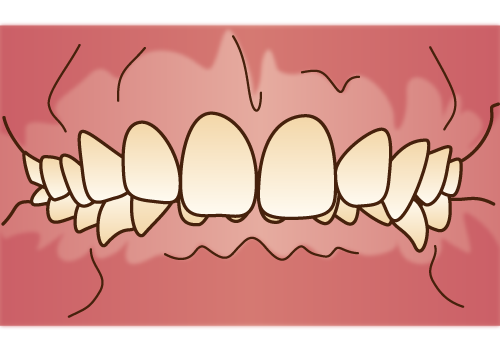

開咬

開咬とは、奥歯で噛んだときに上下の前歯の間に空間ができている状態です。前歯で食べ物を噛み切れず、結果的に奥歯への負担が増加します。子どもの頃から奥歯への負担が蓄積すると、奥歯を早期に失う恐れがあります。また、口の中に空気が入りやすくなるため、乾燥によって唾液が減少し、むし歯のリスクが高まる点にも注意が必要です。

開咬とは、奥歯で噛んだときに上下の前歯の間に空間ができている状態です。前歯で食べ物を噛み切れず、結果的に奥歯への負担が増加します。子どもの頃から奥歯への負担が蓄積すると、奥歯を早期に失う恐れがあります。また、口の中に空気が入りやすくなるため、乾燥によって唾液が減少し、むし歯のリスクが高まる点にも注意が必要です。